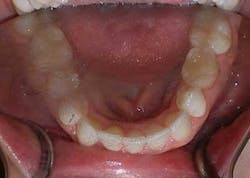

As noted above, the patient had a retained primary molar. Since the primary molar had larger mesial-distal dimensions than a second premolar, the completed treatment resulted in an acceptable compromise of interdigitation on this side. Treatment progressed very well, although a refinement was needed to finish the positioning of the lower right cuspid at the end of treatment (Figs. 9-16). The patient was given final upper and lower in-house thermoformed retainers to wear at night. Then a few months later, a permanent lingual retainer was bonded at the patient’s request on the lower from cuspid to cuspid.

Figs. 9-16